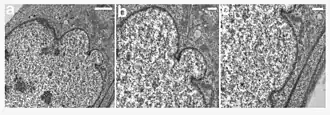

| A young girl with progeria (left). A healthy cell nucleus (right, top) and a progeric cell nucleus (right, bottom). | |

HGPS is caused by mutations that weaken the structure of the cell nucleus, making normal cell division difficult. The histone mark H4K20me3 is involved and caused by de novo mutations that occur in a gene that encodes lamin A. Lamin A is made but is not processed properly. This poor processing creates an abnormal nuclear morphology and disorganized heterochromatin. Patients also do not have appropriate DNA repair, and they also have increased genomic instability.[14]

In HGPS, the recognition site that the enzyme requires for cleavage of prelamin A to lamin A is mutated. Lamin A cannot be produced, and prelamin A builds up on the nuclear membrane, causing a characteristic nuclear blebbing.[37] This results in the symptoms of progeria, although the relationship between the misshapen nucleus and the symptoms is not known.

A study that compared HGPS patient cells with the skin cells from young and elderly normal human subjects found similar defects in the HGPS and elderly cells, including down-regulation of certain nuclear proteins, increased DNA damage, and demethylation of histone, leading to reduced heterochromatin.[38] Nematodes over their lifespan show progressive lamin changes comparable to HGPS in all cells but neurons and gametes.[39] These studies suggest that lamin A defects are associated with normal aging.[38][40]